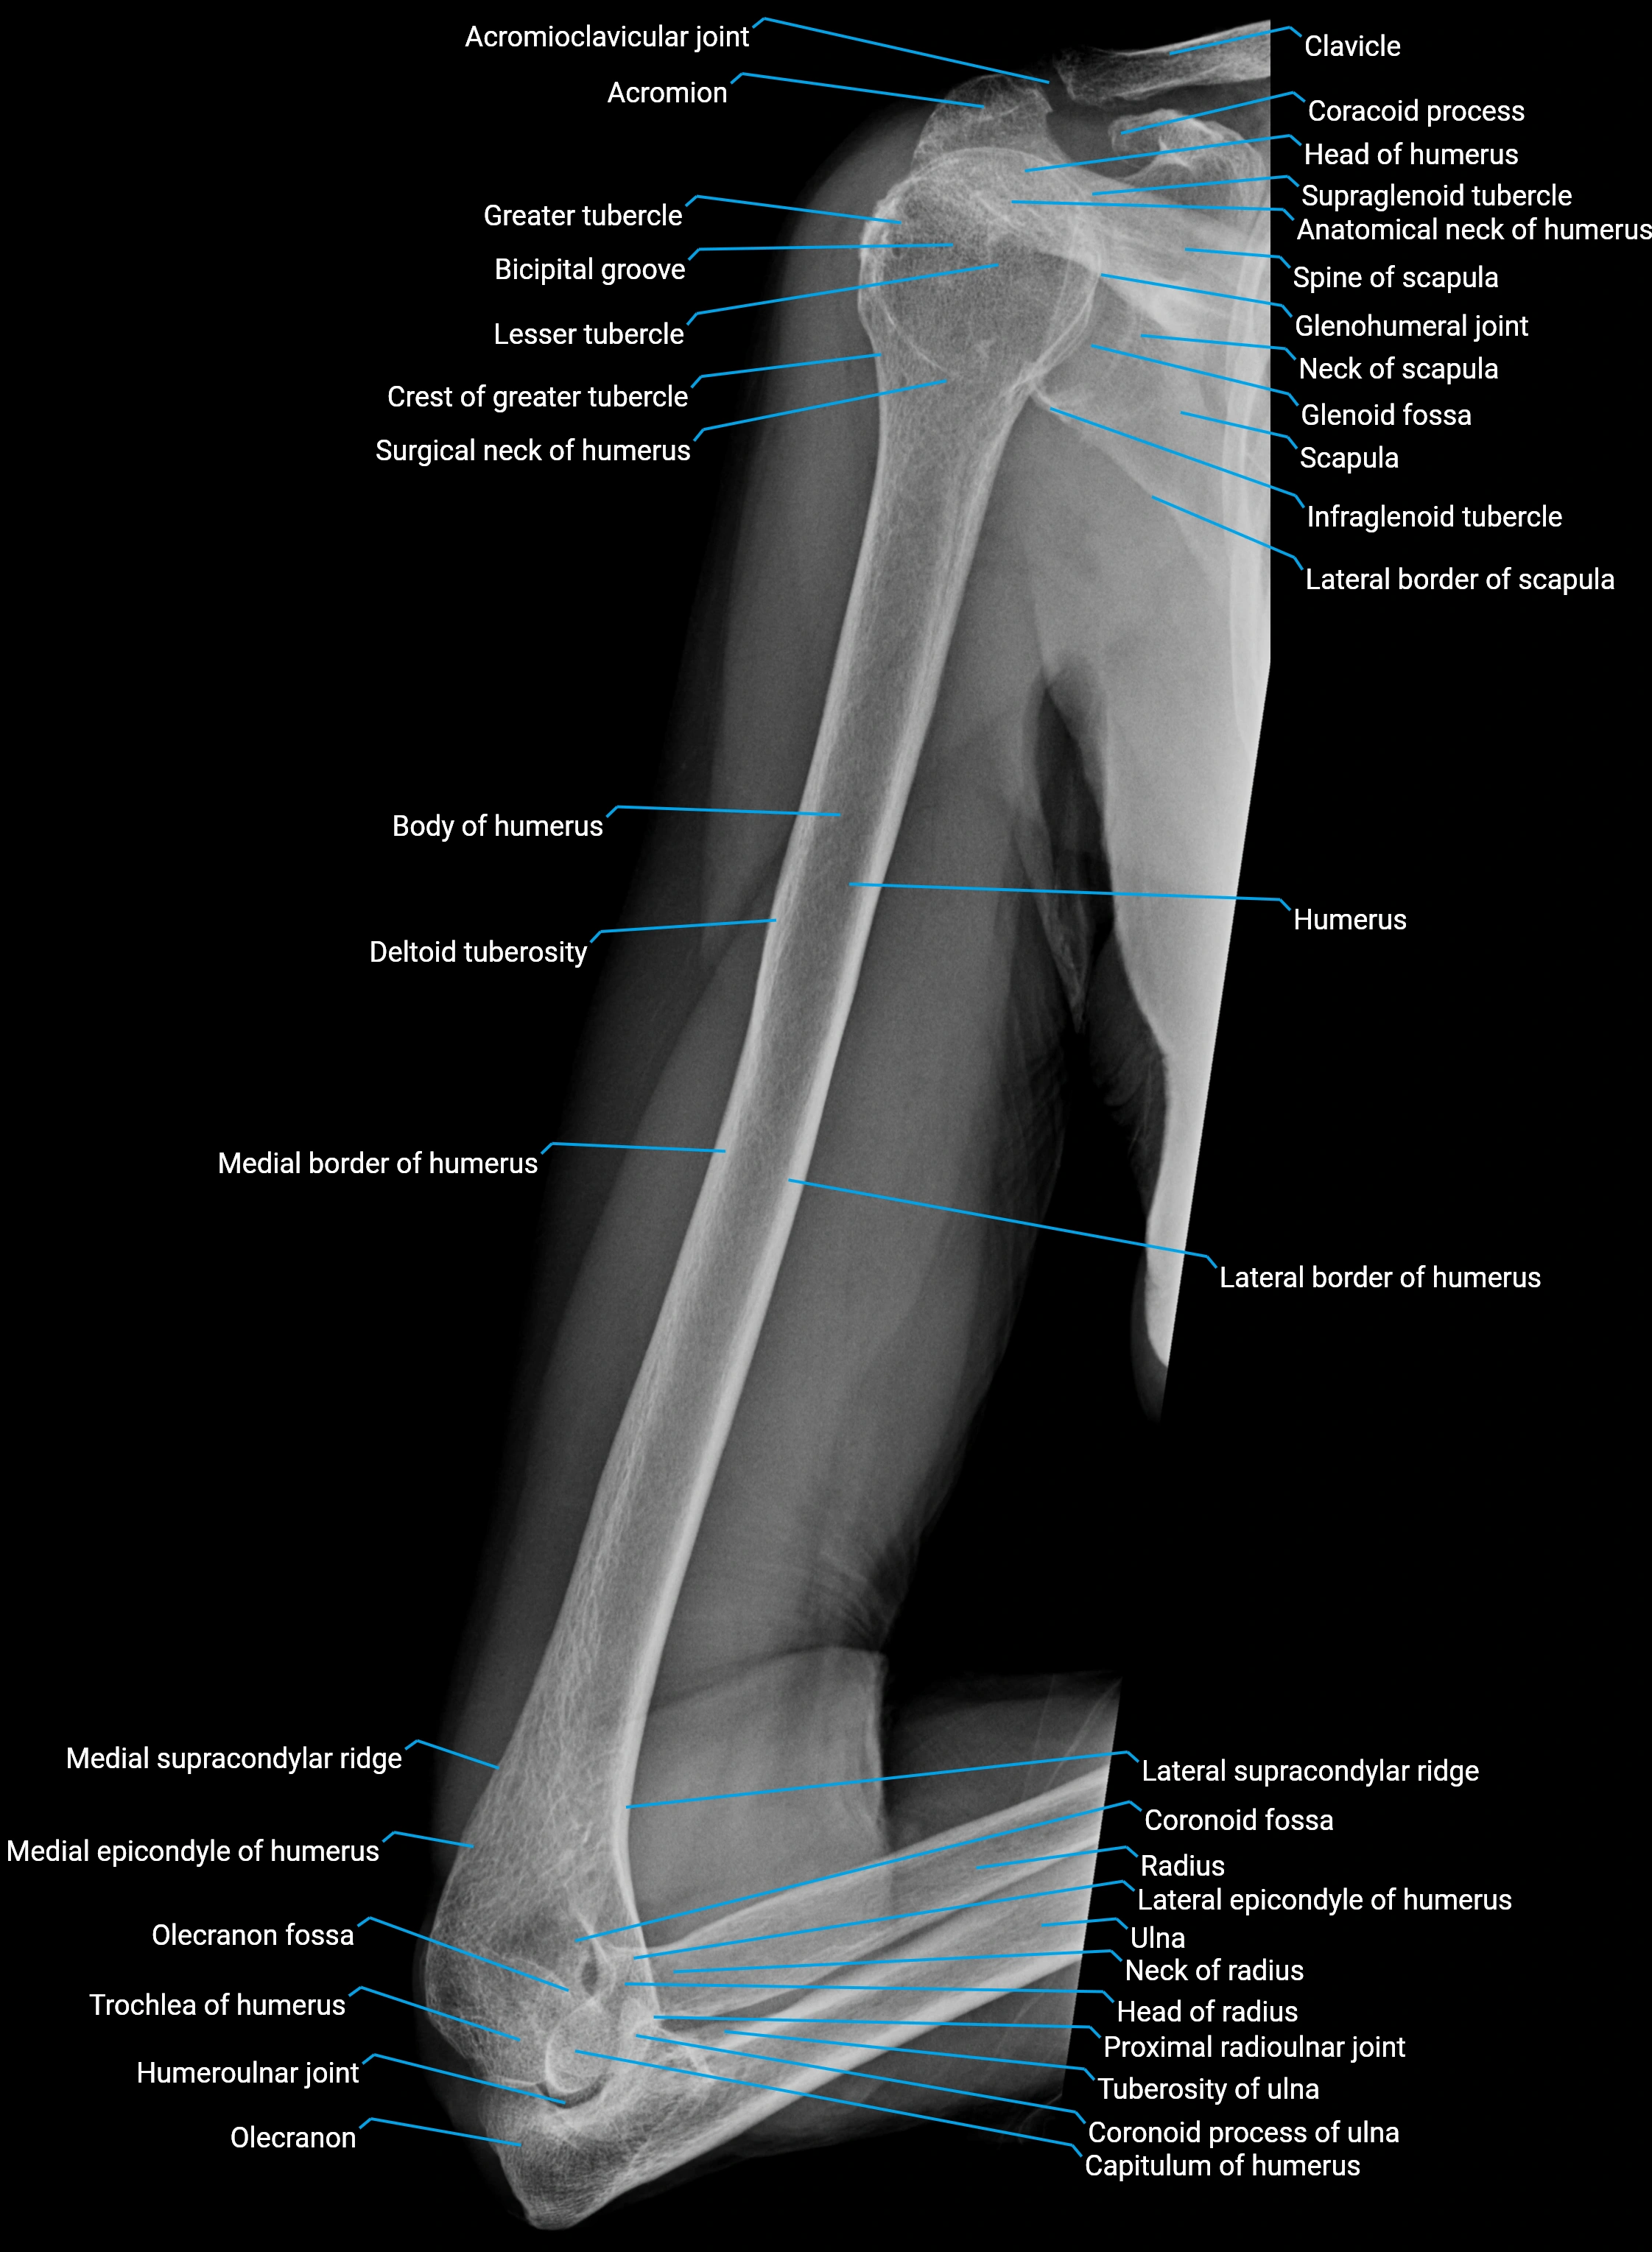

The acromial part of the deltoid muscle (also known as the middle or lateral part) forms the thick, lateral aspect of the deltoid, giving the shoulder its characteristic rounded contour. It arises from the lateral border and superior surface of the acromion process of the scapula and inserts into the deltoid tuberosity of the humerus.

Origin, Course, and Insertion

• Origin: Lateral border and superior surface of the acromion process of the scapula

• Course: Fibers run vertically downward over the lateral aspect of the shoulder

• Insertion: Deltoid tuberosity on the lateral surface of the humerus, via a thick tendinous attachment